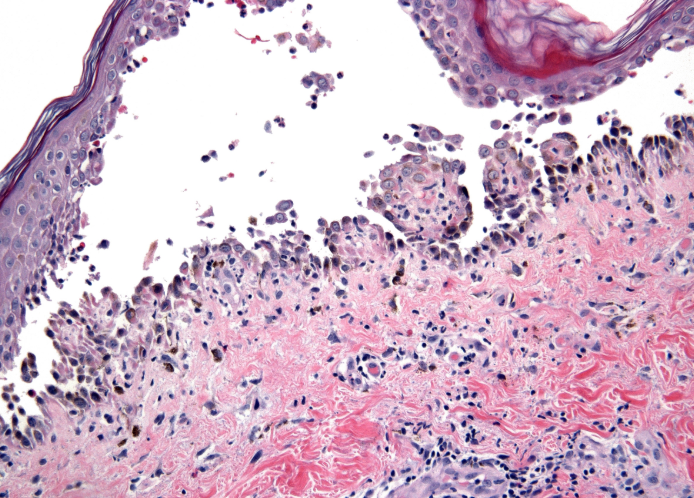

Coupe histologique de l'épiderme d'un patient atteint de Pemphigus Vulgaris :

Ici, tout l'espace blanc constitue une bulle causée par une perte de jonction cellules-cellules au sein de l'épiderme, dû à la destruction des desmogléines desmosomales attaquées par les auto anticorps du Pemphigus Vulgaris.